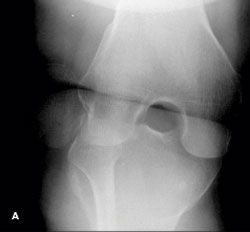

Knee pain following a soccer injury:The frontal radiograph revealsthat the patella is dislocated laterally(A). This is confirmed on the sunriseradiograph (B). A lateral radiographshows the malalignment of the patellawith the distal femur (C). Mostimportant, it also shows no fracture.Lateral dislocation of the patella isdiagnosed.

Outcome of this case. The patient'sdislocation was reduced externally.A frontal radiograph of the kneeobtained after the reduction showsnormal alignment of the patella andthe distal femur (D). This is confirmedby a post-reduction lateral view (E).At 3 months, the patient has not hada recurrence.